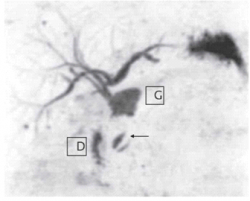

| תצלום 8.8: Percutanous trans-hepatic cholangiography (PTC) - תמונה שמאלית החץ מצביע על המחט והצנתר המוחדרים לדרכי המרה תמונה ימנית חץ מצביע על פגם בדרכי המרה G-כיס מרה 1- צינור מרה משותף. | |

- Percutaneus trans-hepatic cholangiography (PTC) (תצלום 8.8). בשיטה זו אפשר להדגים את דרכי המרה על-ידי ניקור מלעורי של הכבד. בניקור חודרים לכלי מרה בכבד ודרכו מזריקים חומר ניגוד לדרכי המרה ה"צובע" את העץ הביליארי. שיטה זו טובה בלוקים בערכי בילירובין גבוהים, שכן בהם אין לבצע את בדיקות הניגוד.

- בשיטה זו ניתן לבצע גם ניקוז קבוע של דרכי המרה על-ידי החדרת נקז לתוך דרכי המרה (PTD - percutaneus trans-hepatic drainage). התנאי להצלחת הבדיקה הוא דרכי מרה מורחבות, שאפשר לזהות בבדיקת אולטרה-סאונד של דרכי המרה (תמונה 9.8).

- בגישה זו אפשר גם לנקז את כיס המרה בחולים עם חסימות בצינור כיס המרה (איור 4.8) או לשלוף אבנים בעזרת מכשיר מיוחד ללכידת אבנים (Basket) (תצלום 10.8).